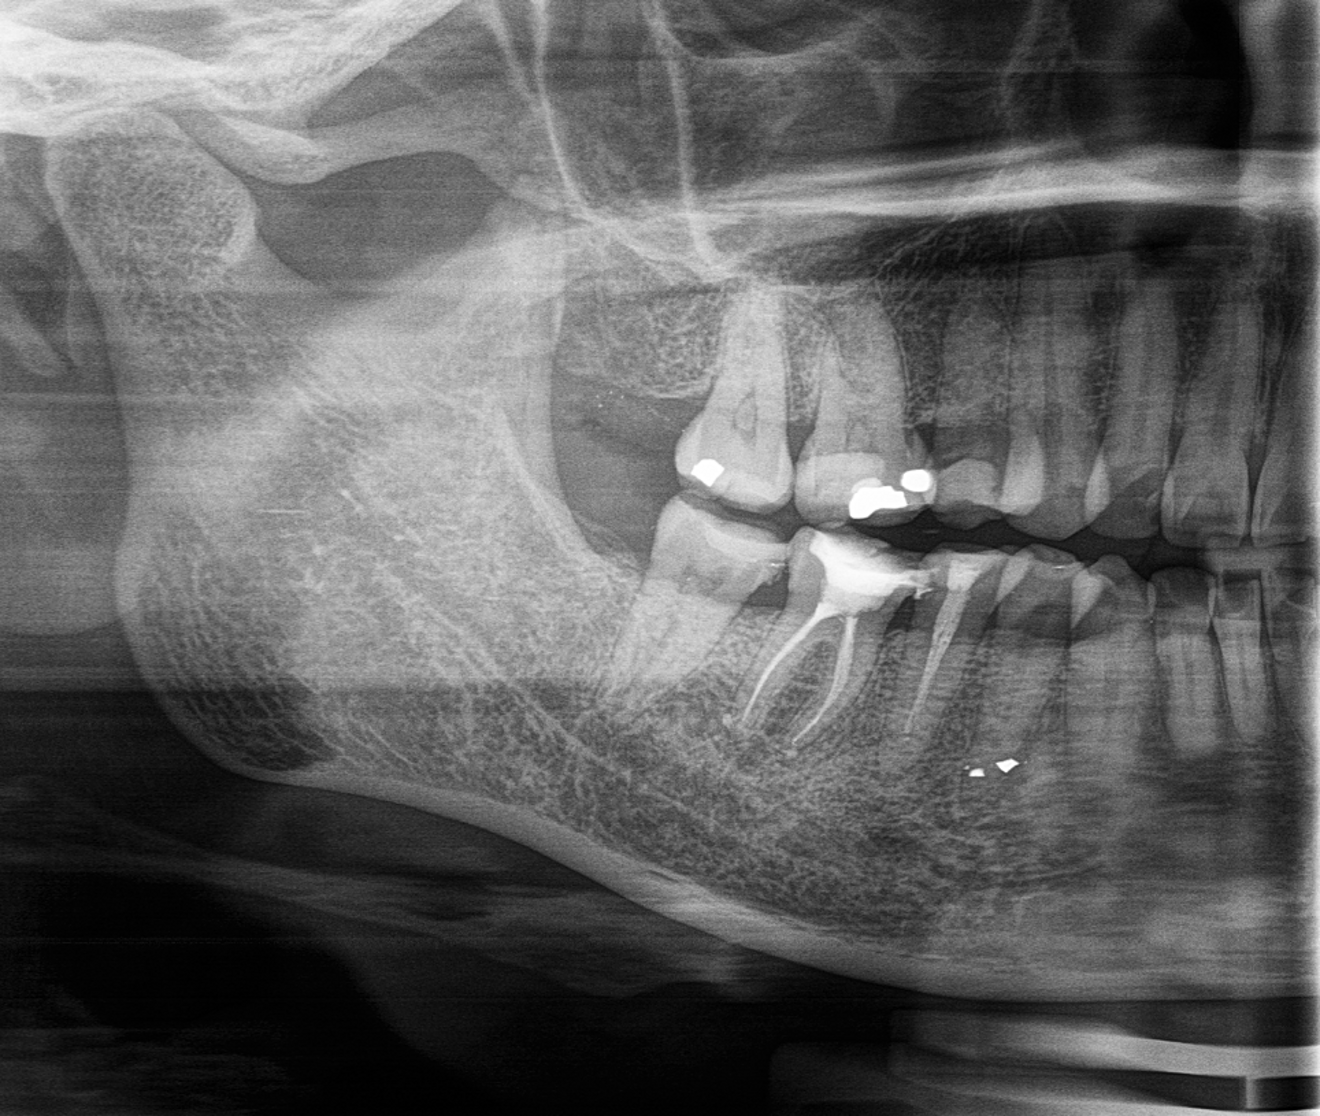

Fig. 2: Access to the pulp chamber showing four canals.

A total of four canals were identified (Fig. 2). The treatment started with continuous delivery of sodium hypochlorite (NaClO) solution (3 ml) by syringe and simultaneous activation by Er:YAG laser. Laser-assisted irrigation was performed with a LightWalker AT-S (Fotona) and an Er:YAG H14 handpiece with a flat SWEEPS 400/9 fibre tip positioned safely at the entrance to the pulp orifice (Table 1). For the shaping of the root canal system, the ProTaper Gold rotary file system (Dentsply Sirona) was used. Minimally invasive root canal preparation began with the 19/0.04 SX file to relocate the coronal aspect of the canals. Cleaning and shaping of the canals were subsequently performed with the 18/0.02 S1 file and 20/0.07 F1 file to the working length.